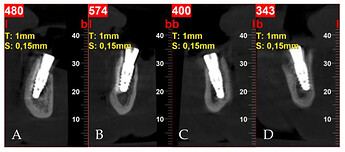

Postoperative cross-sectional CBCT scans: (A) tooth 32; (B) tooth 34; (C) tooth 42; (D) tooth 44.